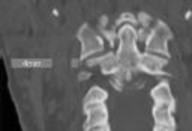

CLINICAL SITUATION

Figure 1 shows a CT from the cervical spine of an 85-year-old woman who fell from a standing height 1 week earlier. She is independent and ambulatory and resides in an assisted living facility. She reports persistent neck pain but denies arm pain or weakness. She is neurologically intact.

Fractures in this region of C2 have a high risk of

Discussion: C

Increased displacement and angulation of odontoid fractures have an increased risk of nonunion. Surgical stabilization has reduced the risks of mortality without increasing the risk of complications compared with nonsurgical treatment options. When treating odontoid fractures, halo vest

immobilization has been shown to increase the risk of dysphagia in the elderly.

Question 7 of 100

4. posterior C1-2 arthrodesis. Discussion: D

Increased displacement and angulation of odontoid fractures have an increased risk of nonunion. Surgical stabilization has reduced the risks of mortality without increasing the risk of complications compared with nonsurgical treatment options. When treating odontoid fractures, halo vest immobilization has been shown to increase the risk of dysphagia in the elderly.

Question 8 of 100

4. Dysphonia Discussion: B

Increased displacement and angulation of odontoid fractures have an increased risk of nonunion. Surgical stabilization has reduced the risks of mortality without increasing the risk of complications compared with nonsurgical treatment